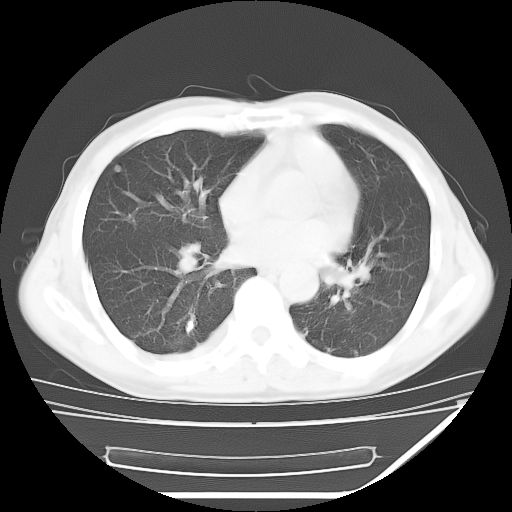

男,59岁,“结核性胸膜炎”30余年,胸部经常疼痛,多次x检查提示“肺部”炎症。腹部疼痛5日,b超提示:“肝内短管结石,余显示不清,建议进一步检查。”

两肺结核并右侧胸腔积液;脾脏、腹腔及腹膜后淋巴结结核[陈旧性];肝内胆管结石

胸部腹部都是结核(双肺。纵隔淋巴结,肝脏,脾脏,肠系膜)